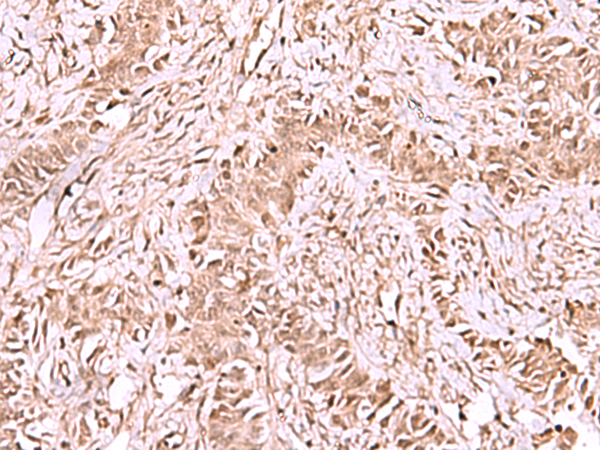

分类: 科研抗体货号: P00258别名: TAK, C-2k, CTK1, CDC2L4, PITALRE应用: WB反应种属: Human, Mouse, Rat